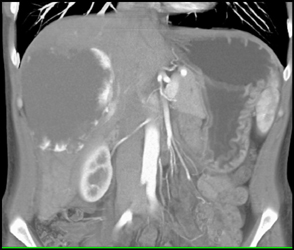

Hemangioma